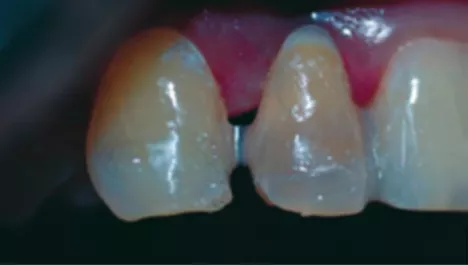

FIG 5:

The extraction socket just after extraction of tooth #12. There was no buccal cortical bone. Curettage was performed to remove perapical cyst and granulation tissue. PRF grafting was done for better tissue healing and one week’s waiting time was observed post extraction.